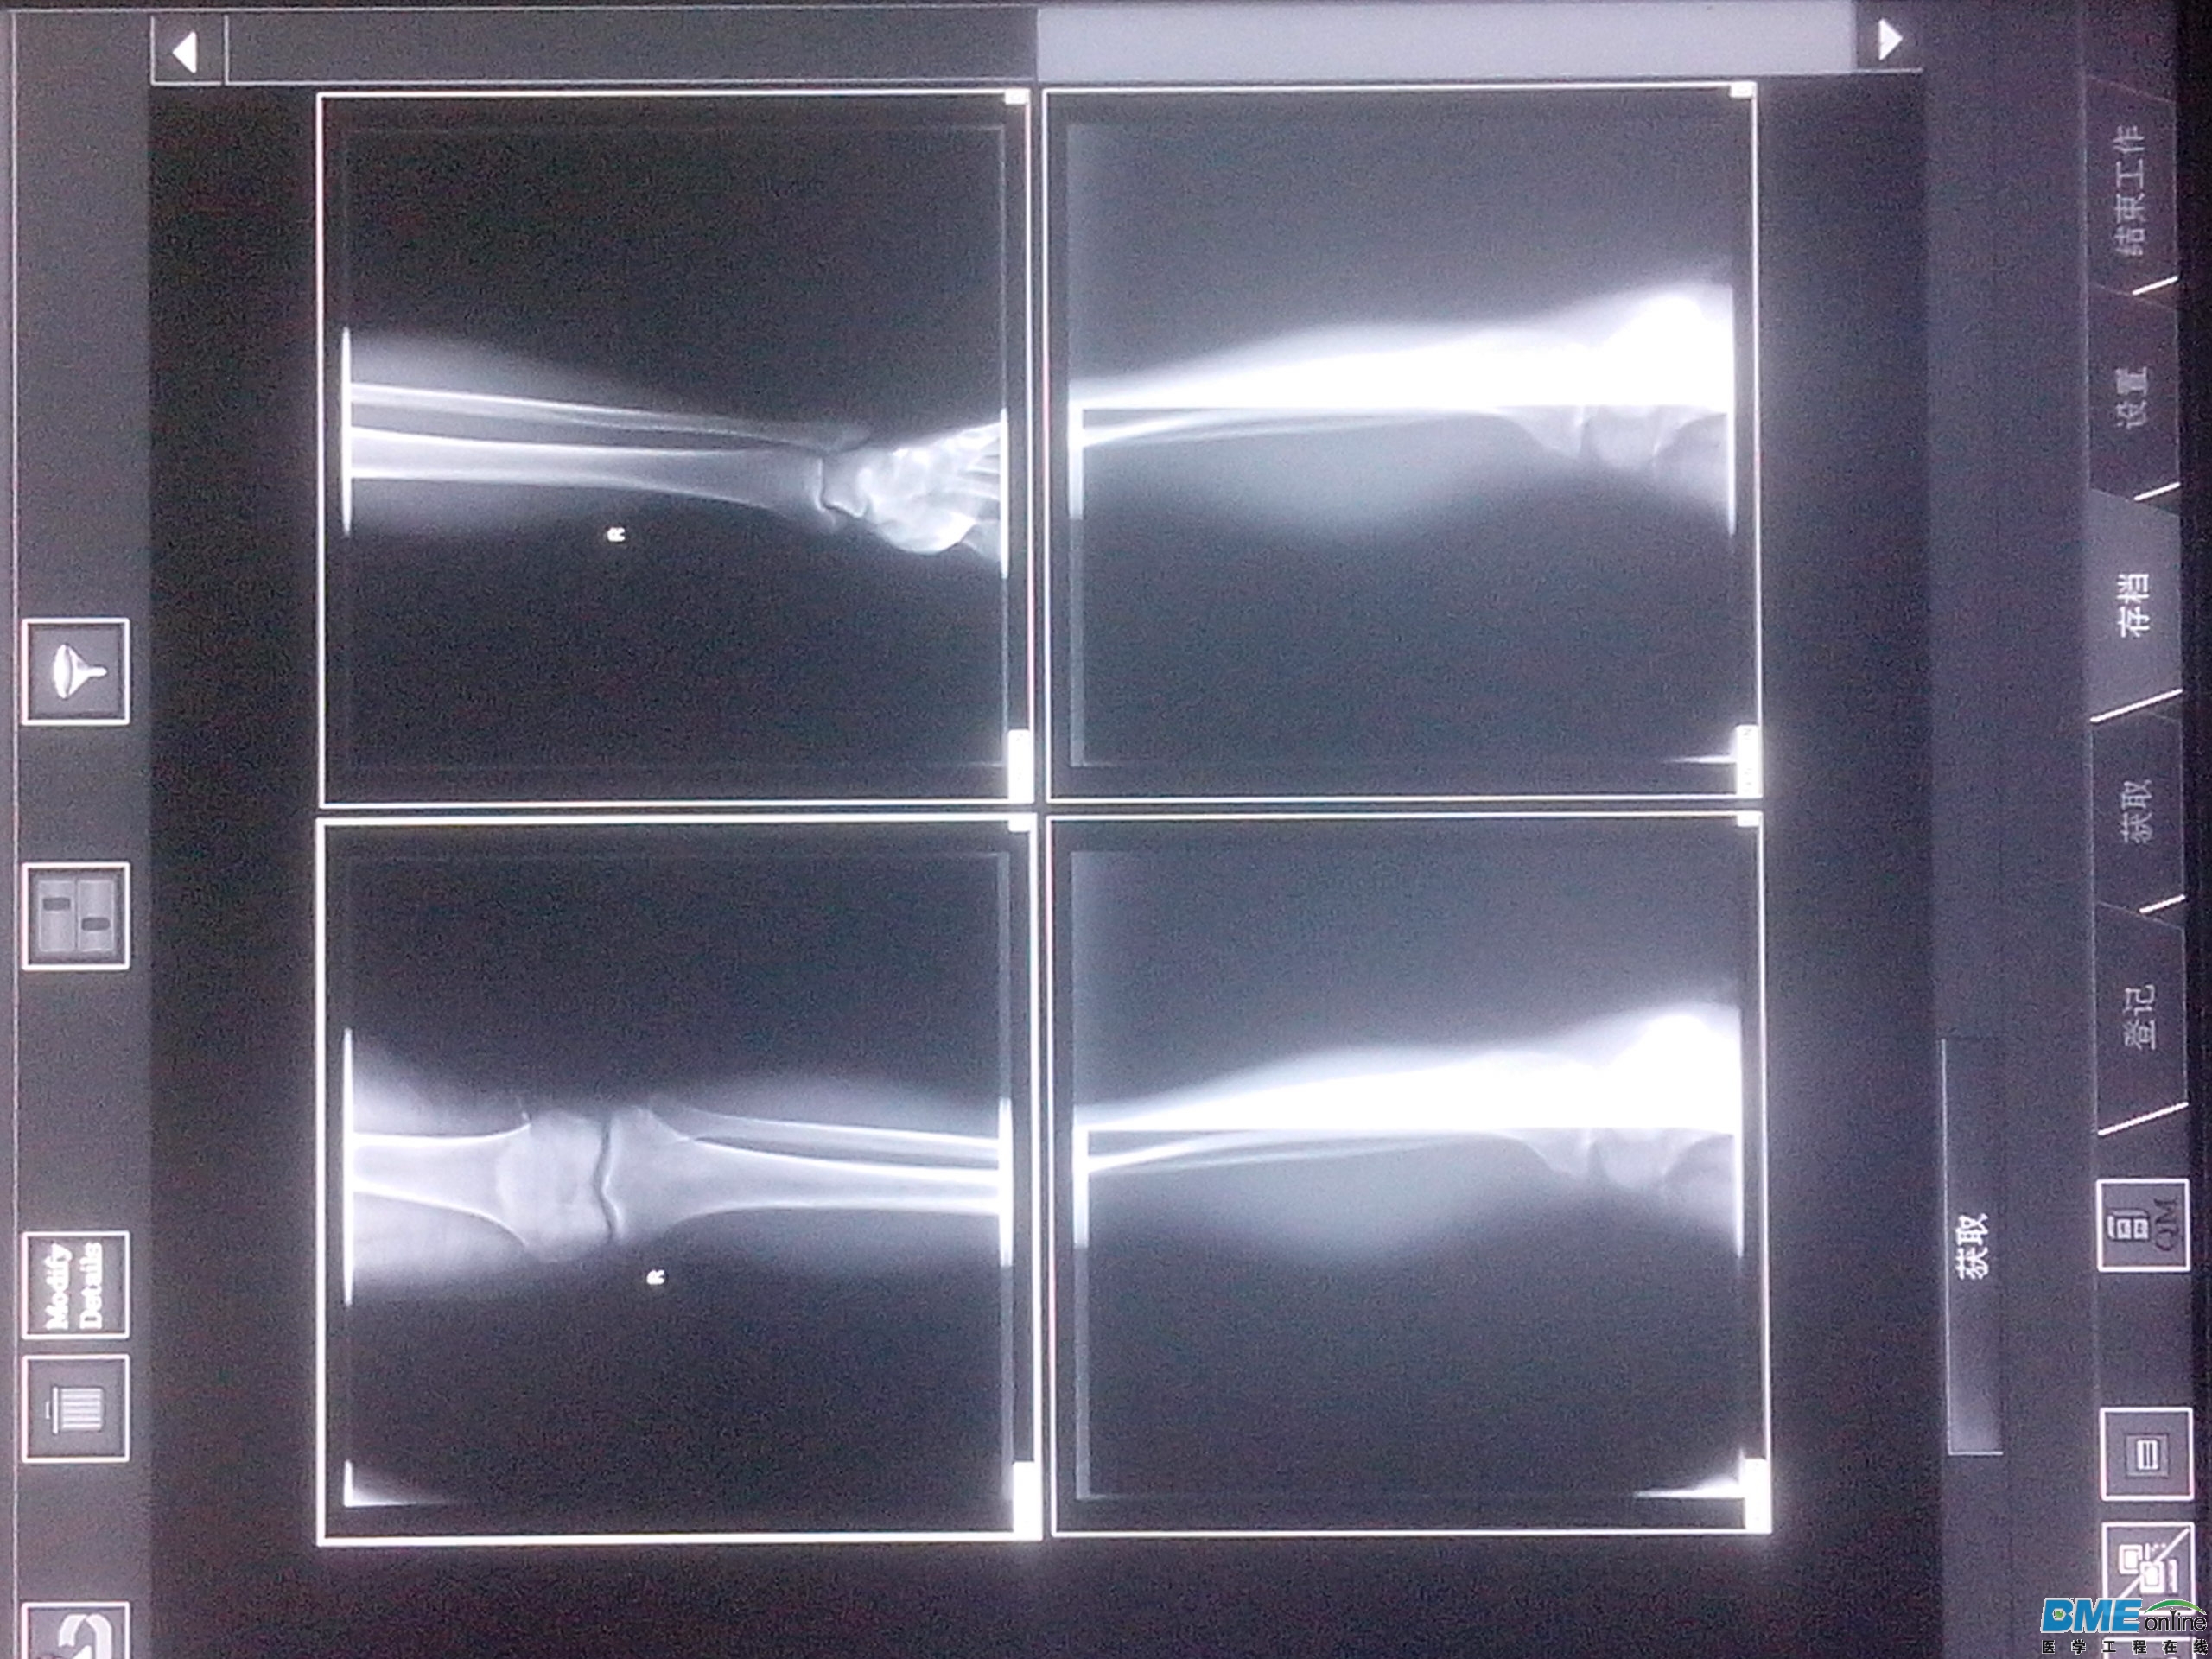

请教高手:这种现象怎么回事!经常发生

好像是KV太低。

几幅影像的曝光条件一样吗、多少,曝光时控制台仪表显示是否正常,X线管使用几年、哪级医院、此类故障累计多长时间